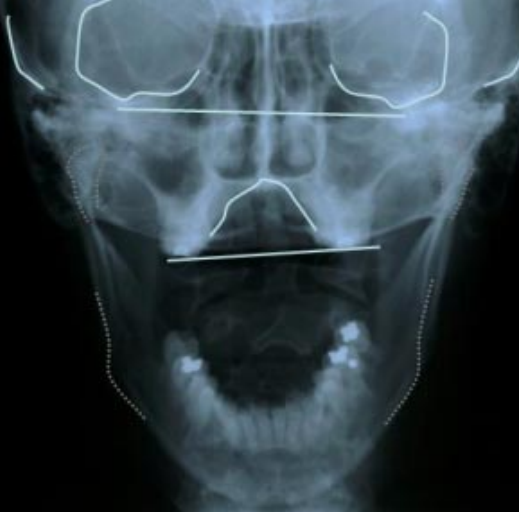

Your skull isn’t a solid block. It’s made of moving bones that shift, adapt, and respond to pressure throughout your life. But over time they can twist and get locked into a misalignment, which is called a cranial strain. You were not born with it, and no amount of creams, generic massages, or sleeping on your back will fix it because it is no longer the soft tissue which is causing the issue.

You have to address the sutures.

We'll reveal which bones sit where (affecting eye height or ear flare) and which muscles are underused (weak and failing to pull symmetrically). You'll finally understand why your face looks the way it does on one side and what you need to correct it.